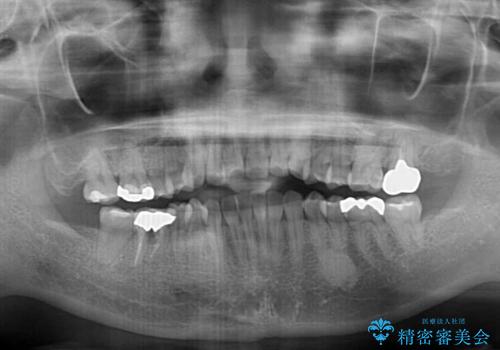

前歯のデコボコとクロスバイト インビザラインによる矯正治療

- 上下のクロスバイトと前歯のデコボコを気にして来院された患者様です。

骨格的に下顎がやや前方にあり、奥歯にクラウンが装着されているため、矯正治療後半の不安定な咬み合わせを避けるのであればワイヤー矯正がおすすめとなりますが、希望によりインビザラインにて治療を行うこととしました。

インビザラインを用い、IPR(歯と歯の間を削る)と歯列全体を拡大させることで、歯並びを整えていくこととしました。

懸念されたとおり、右下のクラウン部分が全く咬み合わず、仕上げの段階で治療期間が長くなりました。